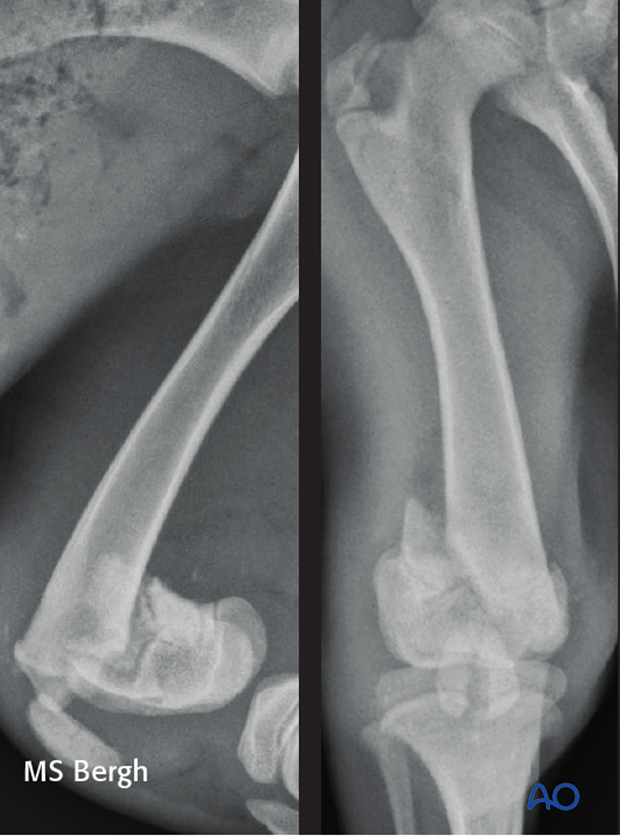

5.5-month-old mixed breed dog presented for right pelvic limb lameness after being hit by a car, with a 33-A2 fracture and a sagittal fracture of the patella.

The fracture was repaired using cross pins. Note the pins cross proximal to the fracture plane. Intraoperatively the articular cartilage of the patella was intact, and the patellar fracture was managed conservatively.

The patient was reported healed uneventfully.